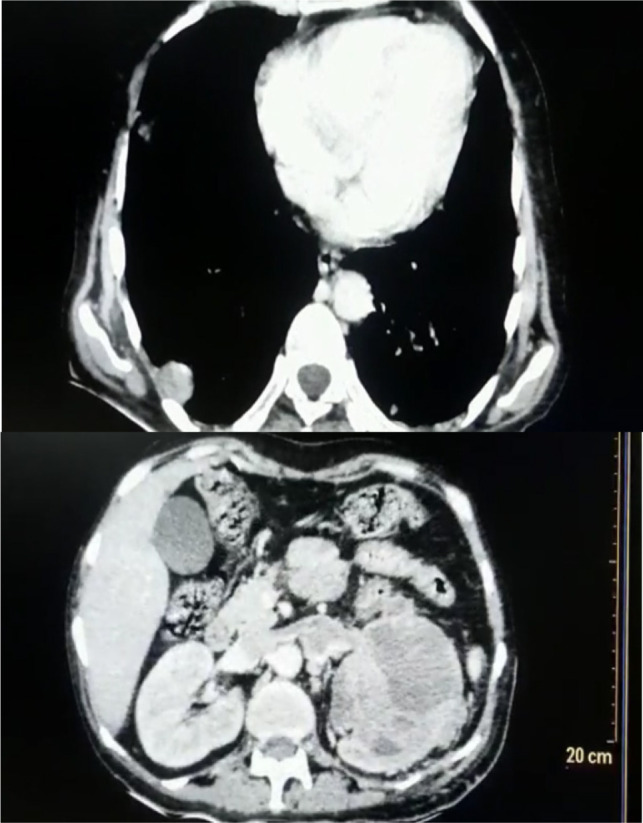

We describe here an atypical case of pyonephrosis which on further evaluation turned out to be a renal cell carcinoma (RCC). The clinical presentation of the patient was that of an infective etiology. However, the renal mass associated with renal vein thrombus and lung metastasis was later diagnosed based on the clinical deterioration of the patient even after insertion of percutaneous nephrostomy. In this case, an underlying renal cancer was probably complicated secondarily leading to pyonephrosis which was the initial presenting manifestation which led to a delay in diagnosis. Pyonephrosis is usually associated with Xanthogranulomatous pyelonephritis. Association of RCC with pyonephrosis is extremely rare and hence seldom reported. Our patient later on underwent radical nephrectomy and the histopathology report was suggestive of RCC. We have described here the clinical manifestations and diagnostic issues of such a case. This case provides evidence that RCC should be kept as one of the differentials in such patients.